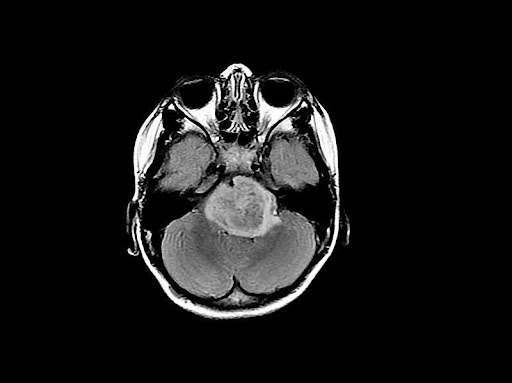

Under the brain tumor spell

Reading time: 5 minutes Mariella Careaga Glioblastoma is a highly aggressive form of cancer that accounts for nearly half of all primary malignant brain tumors in adults (1). Patients diagnosed with this deadly brain cancer have an average survival rate of only 8 months, and it is estimated that glioblastoma claims the lives of more... Continue Reading →

To sync or not to sync: Cancer’s complicated relationship with our internal clocks

Reading time: 5 minutes Andrea Lius For several decades, scientists have observed that disruptions to the body’s internal clock, also known as the circadian rhythm, can promote cancer development and progression.1 They also found that many fast-growing cancers have circadian rhythms that are desynchronized from healthy cells. However, glioblastoma (GBM), a deadly and aggressive type... Continue Reading →